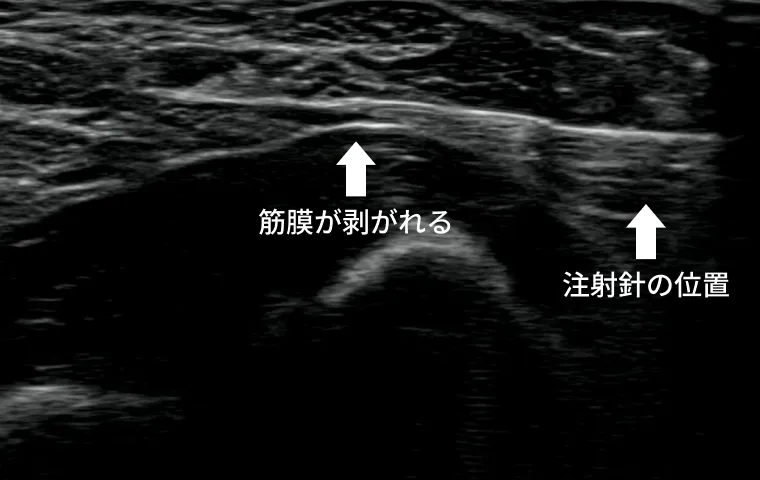

超音波(エコー)検査による観察技術の進歩により、筋膜や神経の滑走障害(こわばり・ひっかかり)をリアルタイムで可視化できるようになりました。

こうした滑走障害を起こしている部位に対して、生理食塩水などを注入しながら組織間の隙間を広げることで、痛みや可動域の制限を改善することが可能です。

【エコー動画】

体液とほぼ同じ浸透圧を持つ生成食塩水を注入し、筋膜を剥がしていきます。

治療部位:肘(尺骨神経)